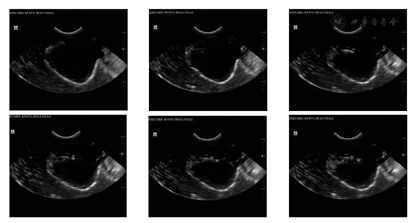

穿刺变形实验采用DP-50全数字便携式超声诊断系统观测盆腔器官群在穿刺实验中的变形情况。实验过程中将超声探头垂直于进针方向由夹具加持在骨盆耻骨联合下方,扫描面为穿刺针与超声探头构成的平面。穿刺过程中的超声影像如图10所示。从图中可清晰观察到穿刺针的进针深度以及前列腺体的变形情况。实验结果证明,盆腔器官群实体模型在超声导航穿刺实验中能够获得较好的图像反馈效果。